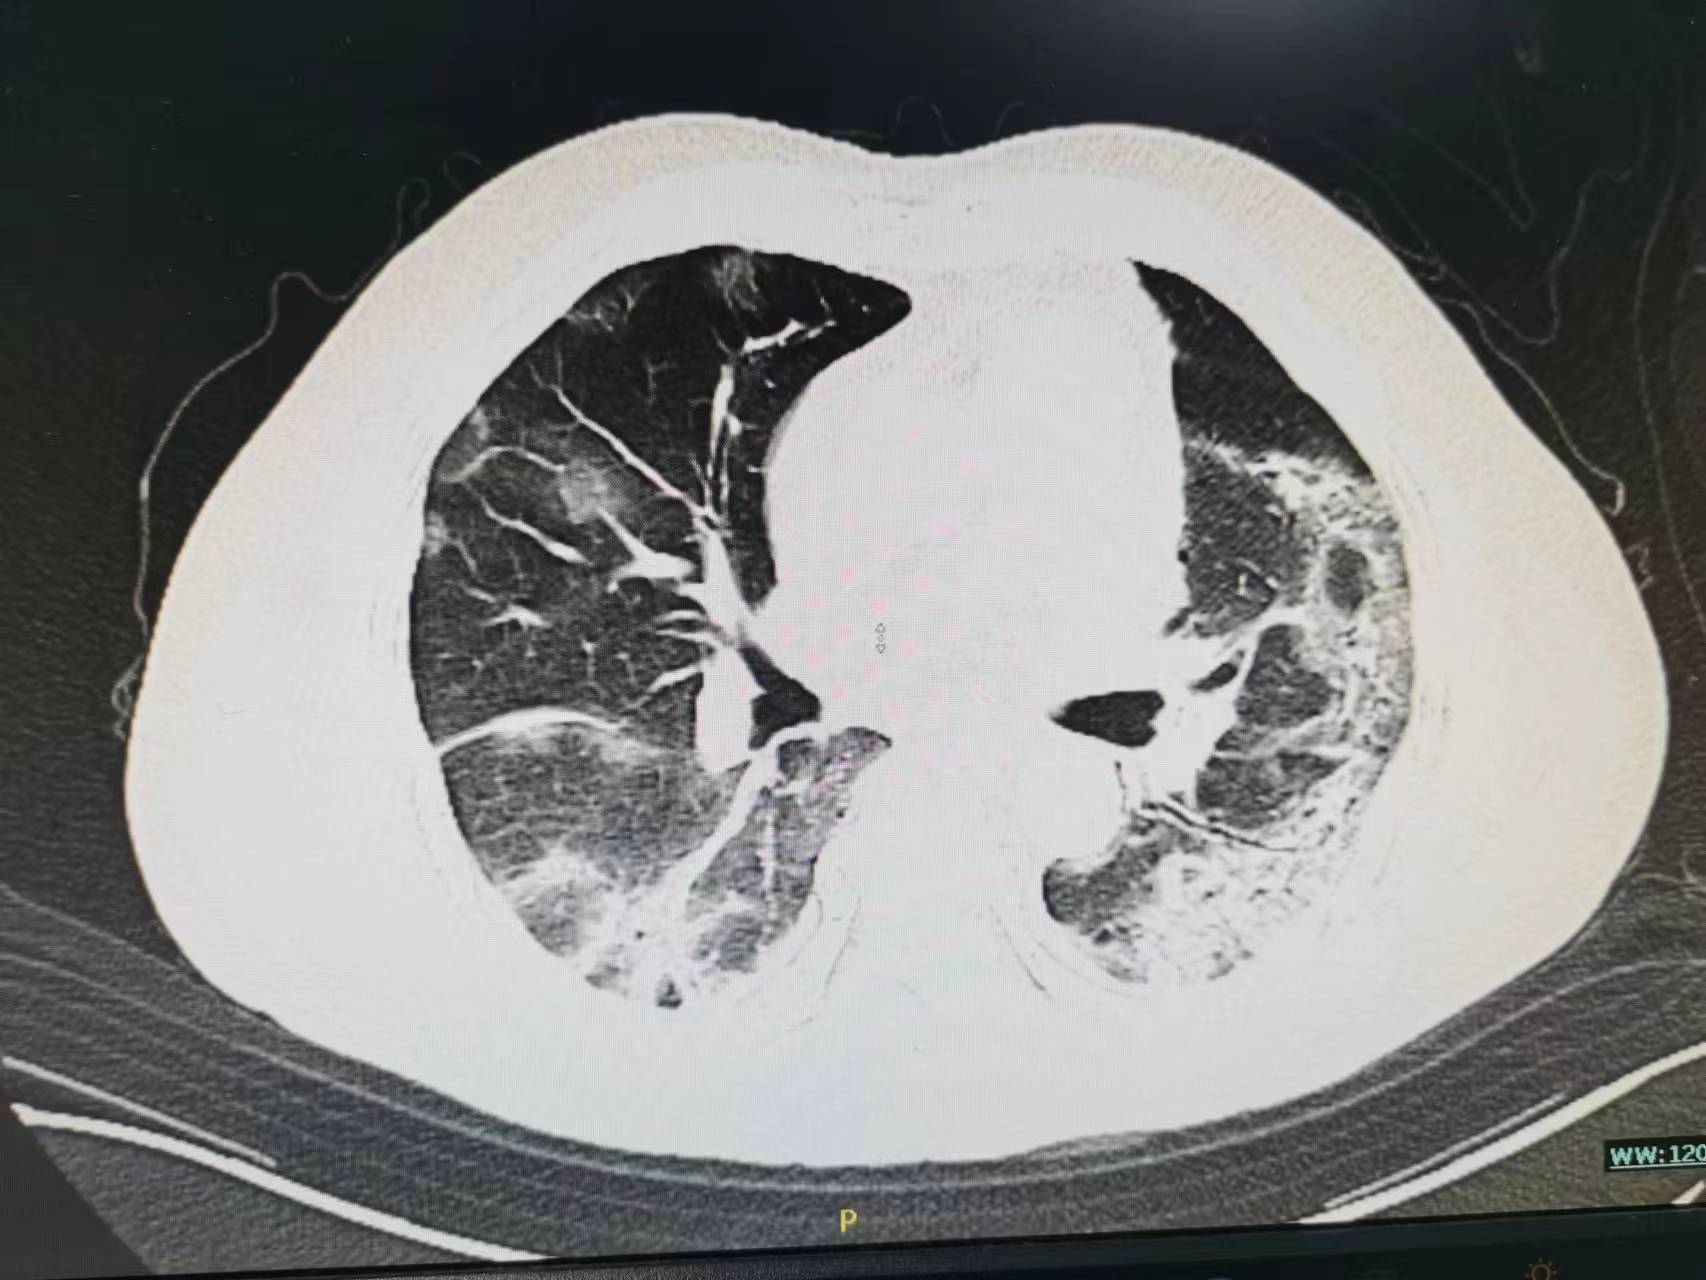

开始家属接受不了,找关系送老太太来医院是为了打“点滴”的,你给我说这个合适吗?病人的情况真有这么重吗?现在老太太不是好好的吗?于是再次向家属讲解病情,重点讲述了病人病情可能的发展并告知可能需要呼吸机,家属还是觉的不可能,查了胸部CT之后才发现病情已如此严重了,基本白肺了。这时候老太太才说这几天感觉到有点“憋的慌”,只是限于不想麻烦孩子的关系不想说,觉的忍忍就过去了。最后还是拗不过家属的要求才来医院的。

一般老年人的症状不典型,如果阳后仍有长时间发热,或出现反复咳嗽、咳痰、精神状态差、食欲差等情况,建议带老人去医院做检查明确一下,比如胸部CT。不建议只是在小诊所输液治疗。这里给大家一个小建议:除了家中常备退热等药物外,建议自备一个指脉氧仪可以随时检测指脉氧,尤其是家中有老人而且伴有高血压、糖尿病等基础病的!!